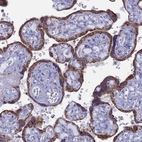

Immunohistochemistry analysis in human placenta and liver tissues using HPA041014 antibody. Corresponding ACSS1 RNA-seq data are presented for the same tissues.